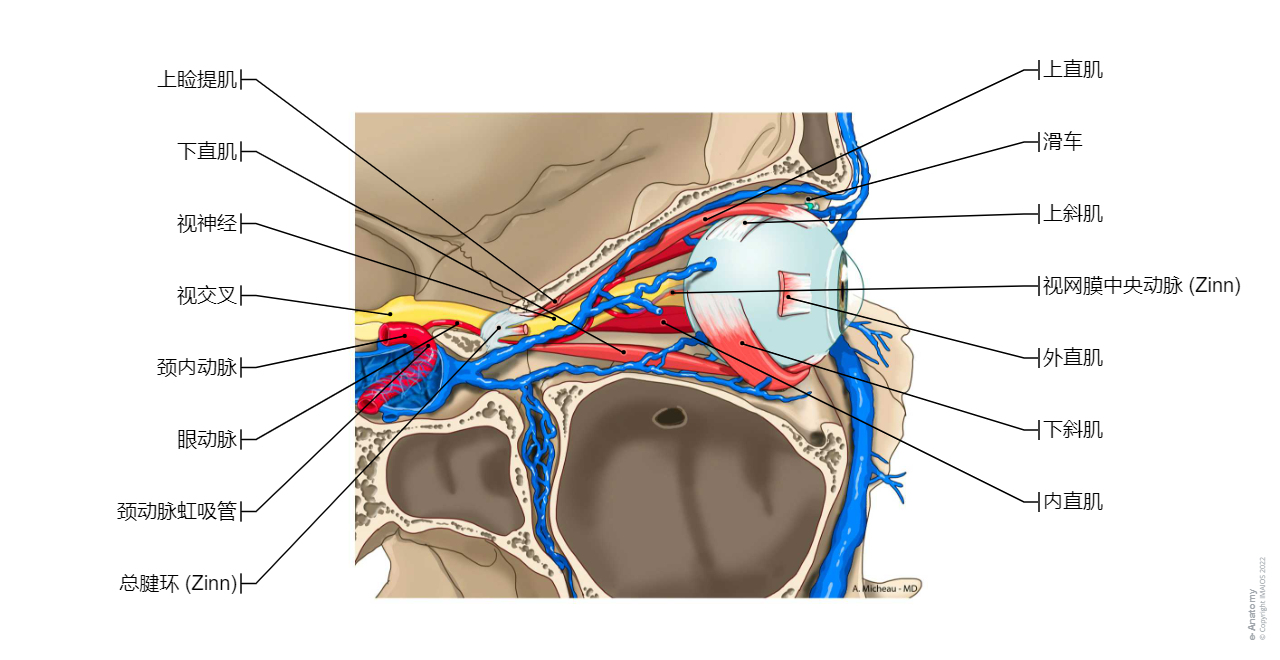

总腱环/秦氏环-眼外肌

眼动脉-解剖

总腱环/秦氏环

眼动脉